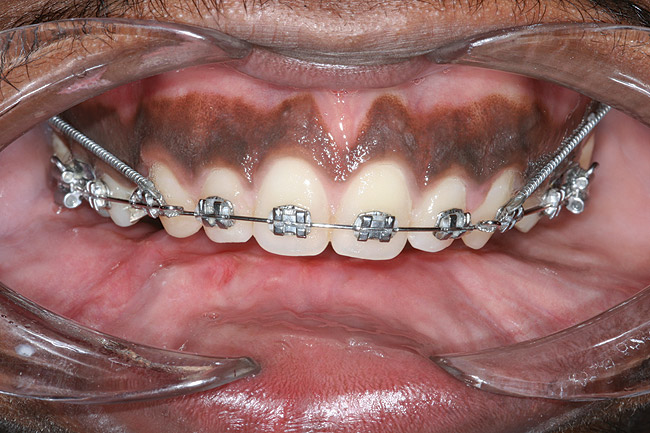

Prior to implant placement, the vertical dimension of occlusion had to be reestablished and a new functional posterior occlusal plane developed. Within this framework, the axial position of the implants could be established. However, the positions of these implants were not solely predetermined by the bony architecture of the newly reconstructed mandible but also could be altered to conform to the proportional harmony of the lower face. To assist in this determination, a left lateral skull film was obtained (Figure 7) and an analysis of facial form, vertical dimension, and incisor position was performed. It was determined that the vertical dimension of the lower face would need to be increased; the posterior occlusal plane would need to be intruded; and the axial position of the lower incisor implants would have to be upright over the newly augmented ridge. In order to establish an esthetic anterior occlusal plane, the upper incisors would have to be retracted without extrusion.9 Final vertical dimension was confirmed by a CBCT scan with a modified surgical guide in place (Figure 8), and this same guide was used for the placement of 10 endosseous dental implants. Then, a transitional lower denture was fabricated and orthodontic treatment was instituted while the implants were allowed to integrate.

Figure 7  Cephalometric x-ray with an analysis of facial form, vertical dimension, and incisor position.

Figure 7